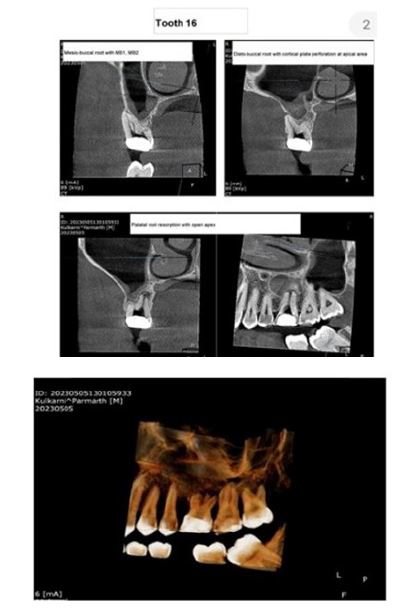

Informed consent was acquired from the patient, following which root canal treatment was initiated for tooth #16 under local anesthesia using 2% lidocaine with 1:80,000 epinephrine (La-Force, Vishal, India). Access was gained using an Endo access bur (Dentsply Maillefer, Ballaigues, Switzerland) mounted on a high-speed handpiece, and the cavity was refined with an Endo-Z bur (Dentsply Maillefer, Ballaigues, Switzerland). Four canal orifices-mesiobuccal 1, mesiobuccal 2, distobuccal, and palatal-were located (Figure 1B). The palatal root showed signs of a wide open apex, prompting referral for a CBCT scan. The CBCT revealed a chronic periapical abscess and external root resorption associated with the palatal root of tooth #16 (Figure 2). Consequently, an apexification procedure was planned for the palatal root, followed by obturation and placement of a full-coverage crown.